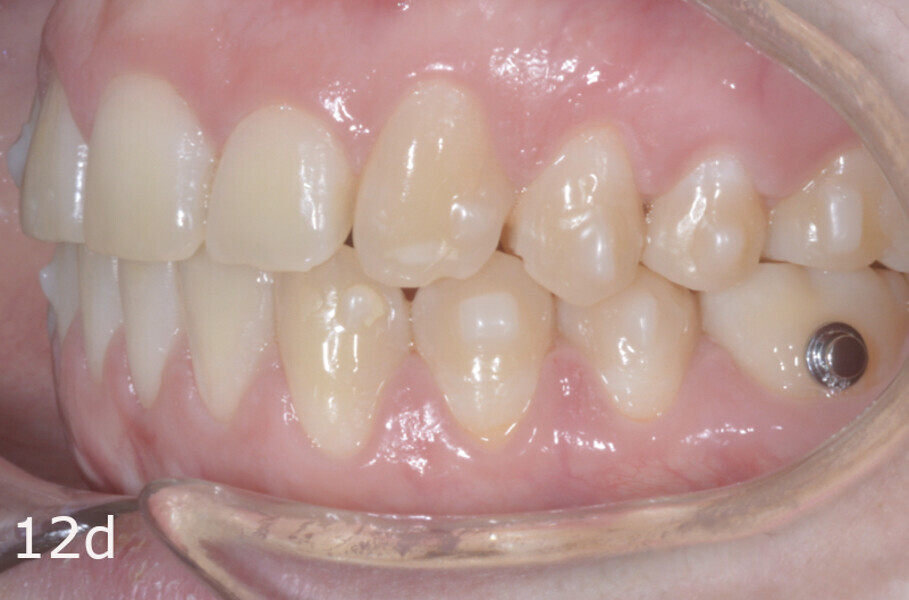

The treatment objectives included closing the anterior open bite, achieving a bilateral Angle Class I relationship and a proper overjet and overbite, correcting the midline discrepancies, and achieving a profile harmonisation. The treatment plan consisted of orthodontic camouflage treatment with asymmetric distalisation in three of the four quadrants using Invisalign aligners (Align Technology) and third molar extraction. The Invisalign Comprehensive package was chosen, and 63 pairs of aligners were used (Figs. 7–10). Each aligner was worn for 20 hours a day for one week each. The use of Class III elastics on both sides was indicated. Afterwards, ten refinement aligners were needed to improve the interdigitation on the right side (Figs. 11 & 12).

The total treatment time was 15 months. An Angle Class I relationship was established along with adequate anterior and canine guidance, establishing a functional occlusion. This not only ensures optimal masticatory function but also protects the teeth and the temporomandibular joint from excessive force. Maxillary and mandibular fixed retention were installed at the end of the treatment (Figs. 13–19).